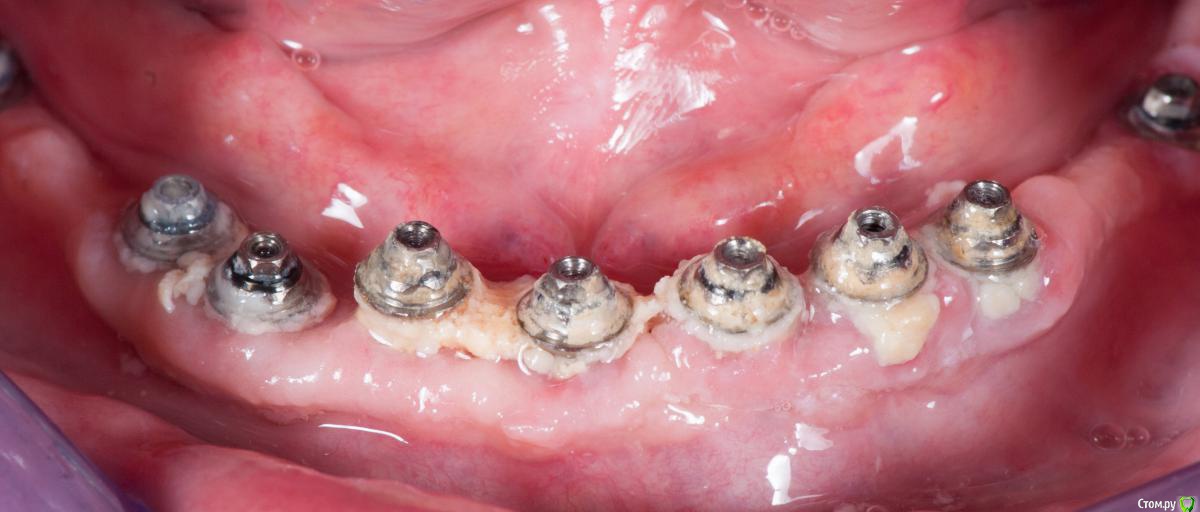

Doc Опубликовано 24 марта, 2015 Поделиться Опубликовано 24 марта, 2015 Попробую обосновать свое заявление. Под рукой нет "все на четырех", но есть все на восьми и девяти. Как раз фотки обрабатываю. Вот одна из самых старых наших работ, когда я еще думал, что мультиюниты это круто. Вот нижняя челюсть. Причем пациент более чем мотивированный. Сам запросил три каппы ночного ношения, чтобы не ломать зубы, купил три ирригатора (по количеству квартир, где спит, видимо), пользуется ирригатором два раза в день. И вот результат. А это тот же самый пациент в тот же день, но с верхней челюстью с уровня имплантов. Правда тогда мы еще внедрение не очень практиковали, но и промывного здесь не было. Тоже диоксид циркония, правда с керамикой, а не с пластмассой. По-моему, разница очевидна. 3 Ссылка на комментарий